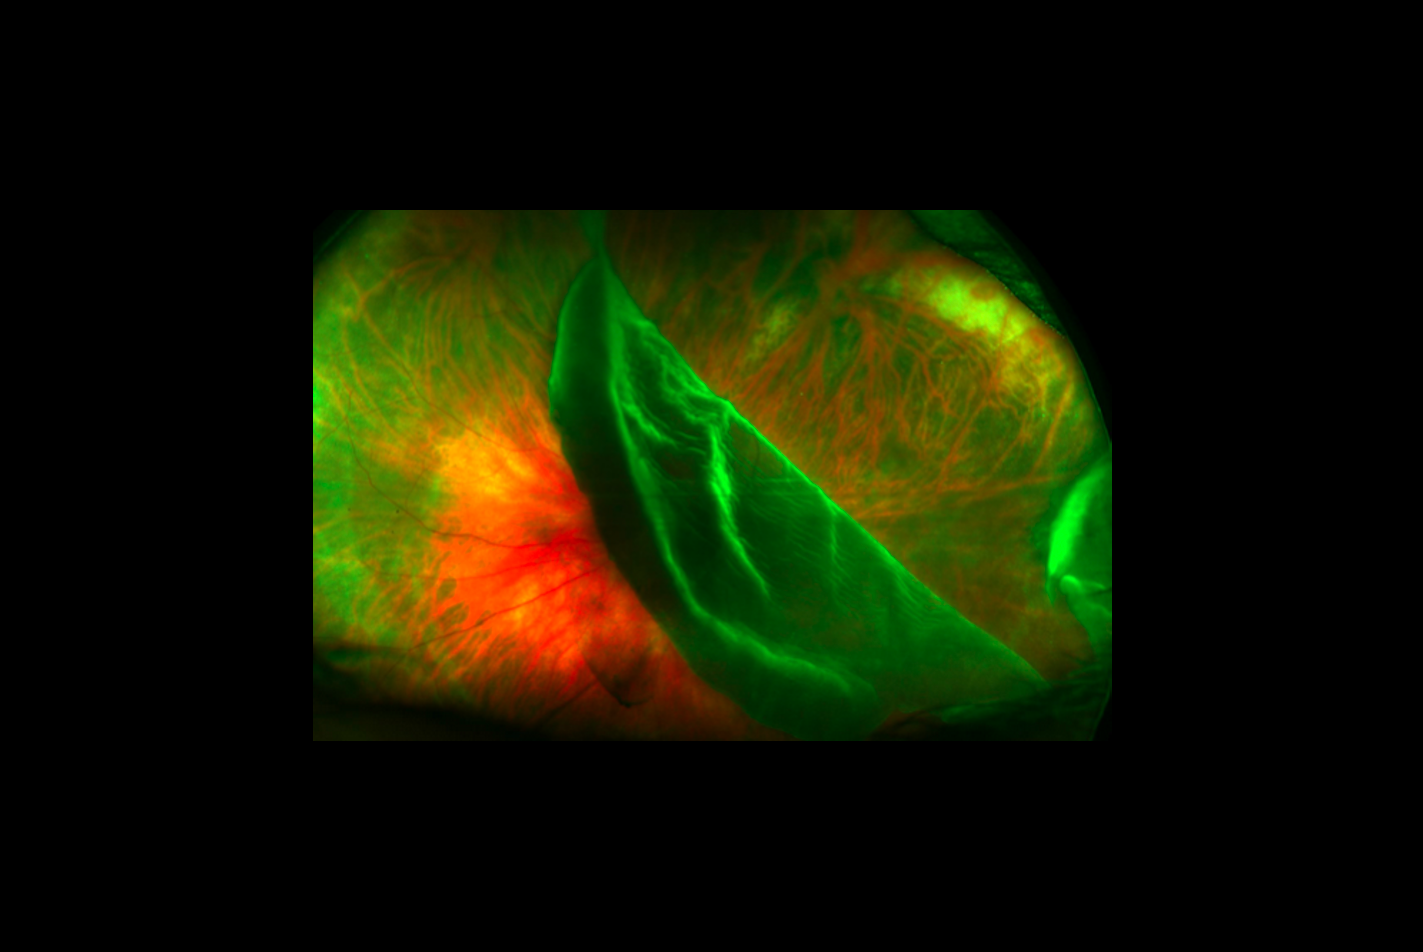

www.sante-sur-le-net.com48: Décollement De Rétine Et Traumatismes à Globe Ouvert | Medicine Key

www.sante-sur-le-net.com48: Décollement De Rétine Et Traumatismes à Globe Ouvert | Medicine Key